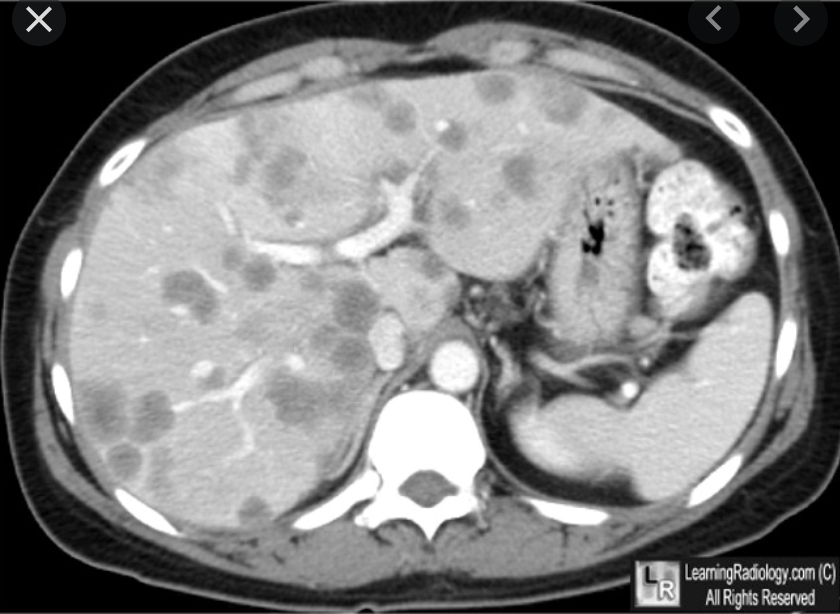

Hepatic infection: candidiasis

Ix: CT app.

Ex: immunocompromised pts., especially those w/hematologic malignancies + chemo.

Ix: CT: tiny hypoattenuating foci which may be rim-enhancing.